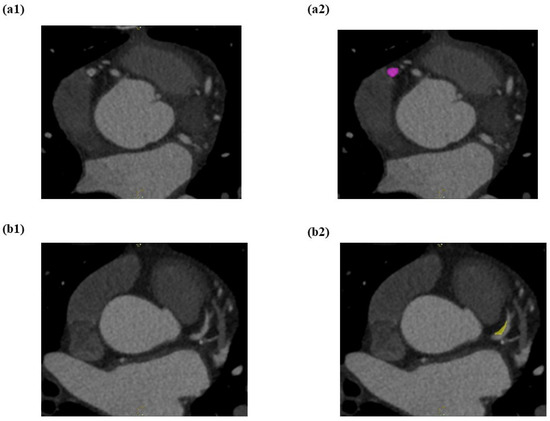

Automated Classification of Atherosclerotic Radiomics Features in Coronary Computed Tomography Angiography (CCTA)

by Mardhiyati Mohd Yunus, Ahmad Khairuddin Mohamed Yusof, Muhd Zaidi Ab Rahman, Xue Jing Koh, Akmal Sabarudin, Puteri N. E. Nohuddin, Kwan Hoong Ng, Mohd Mustafa Awang Kechik and Muhammad Khalis Abdul Karim

Diagnostics 2022, 12(7), 1660; https://doi.org/10.3390/diagnostics12071660 - 8 Jul 2022

Cited by 10 | Viewed by 4109

Abstract

Radiomics is the process of extracting useful quantitative features of high-dimensional data that allows for automated disease classification, including atherosclerotic disease. Hence, this study aimed to quantify and extract the radiomic features from Coronary Computed Tomography Angiography (CCTA) images and to evaluate the [...] Read more.

Radiomics is the process of extracting useful quantitative features of high-dimensional data that allows for automated disease classification, including atherosclerotic disease. Hence, this study aimed to quantify and extract the radiomic features from Coronary Computed Tomography Angiography (CCTA) images and to evaluate the performance of automated machine learning (AutoML) model in classifying the atherosclerotic plaques. In total, 202 patients who underwent CCTA examination at Institut Jantung Negara (IJN) between September 2020 and May 2021 were selected as they met the inclusion criteria. Three primary coronary arteries were segmented on axial sectional images, yielding a total of 606 volume of interest (VOI). Subsequently, the first order, second order, and shape order of radiomic characteristics were extracted for each VOI. Model 1, Model 2, Model 3, and Model 4 were constructed using AutoML-based Tree-Pipeline Optimization Tools (TPOT). The heatmap confusion matrix, recall (sensitivity), precision (PPV), F1 score, accuracy, receiver operating characteristic (ROC), and area under the curve (AUC) were analysed. Notably, Model 1 with the first-order features showed superior performance in classifying the normal coronary arteries (F1 score: 0.88; Inverse F1 score: 0.94), as well as in classifying the calcified (F1 score: 0.78; Inverse F1 score: 0.91) and mixed plaques (F1 score: 0.76; Inverse F1 score: 0.86). Moreover, Model 2 consisting of second-order features was proved useful, specifically in classifying the non-calcified plaques (F1 score: 0.63; Inverse F1 score: 0.92) which are a key point for prediction of cardiac events. Nevertheless, Model 3 comprising the shape-based features did not contribute to the classification of atherosclerotic plaques. Overall, TPOT shown promising capabilities in terms of finding the best pipeline and tailoring the model using CCTA-based radiomic datasets. Full article

(This article belongs to the Section Medical Imaging and Theranostics)

Show Figures

Figure 1